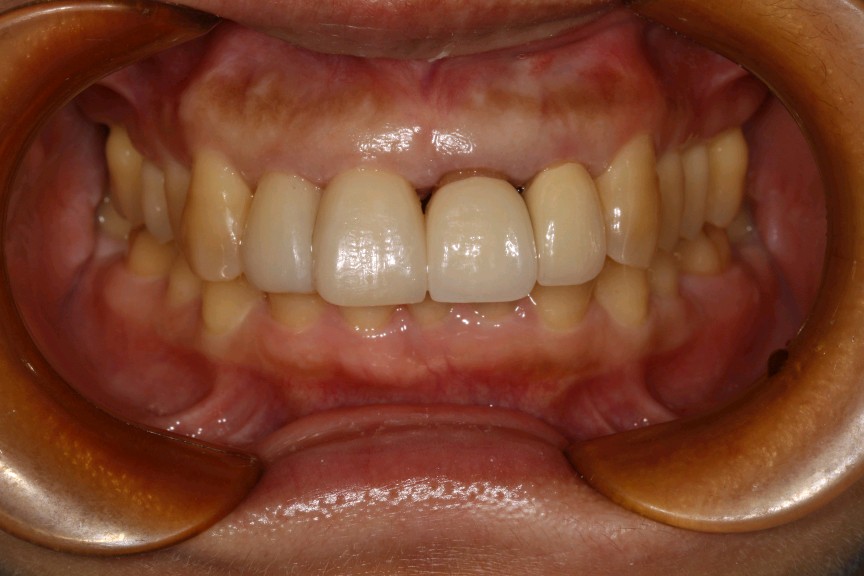

患者女,45岁。患者自述有刷牙出血症状,探易出血,探及牙周袋深度5mm,可探及袋内牙石3mm。21、22已行根管治疗加桩冠修复,牙龈萎缩,边缘不密合,21牙颈部楔缺。中切牙之间缝隙较大。12邻面部分充填物。。X线示根尖无阴影。患者自觉前牙不美观,要求重新修复。

治疗计划:1、牙周治疗。2、21,22饵激光拆除牙冠。清理基牙,重新预备,西诺德全冠修复。3、11、12贴面修复。

这位患者就是错误的刷牙方式,加上牙周炎导致的牙龈萎缩,牙颈部暴露。最终只能拆除重新修复。既费钱又费时间。所以往往一些不起眼的小问题,生活中的一些不良小习惯,日积月累就会出现从小问题发展成大问题。使得前面的工作功亏一篑徒劳无功。一定要谨遵医嘱,使用正确刷牙方式,定期复查,及时发现及时杜绝。